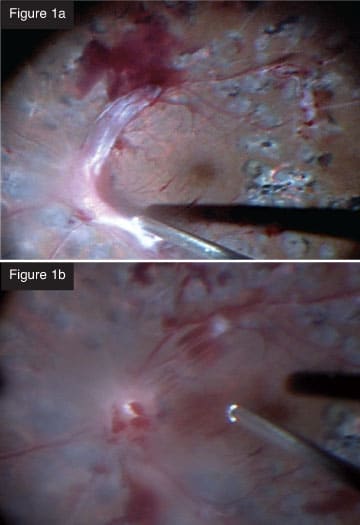

| CASE 1: Combined tractional rhegmatogenous retinal detachment in a diabetic patient. Using the 25+ for a tractional retinal detachment, I can remove thick blood clots efficiently, something that was not possible with the previous vitrectomy systems. The probe is so small, it can get under the membranes so you can dissect them. You can shave them from the surface of the retina in much the same way you would use vertical scissors. You can almost peel them from blood vessels. In a recent case (Figures 1a and 1b), I created a space to lift the fibrovascular membrane, which allowed me to remove it with the cutter. I was able to get very close to the retina with almost no movement, which was unthinkable with our previous technology. After removing the tissue, which was quite thick, I applied diathermy to the breaks, performed fluid-air exchange and applied photocoagulation. A nice feature of the laser is that you can control the intensity of the burns with the foot pedal. This type of case can be done efficiently with minimal complications. The IOP control prevents bleeding from a drop in IOP during instrument exchanges. In the past, we would have had to perform a complicated procedure with a multitude of different instruments.